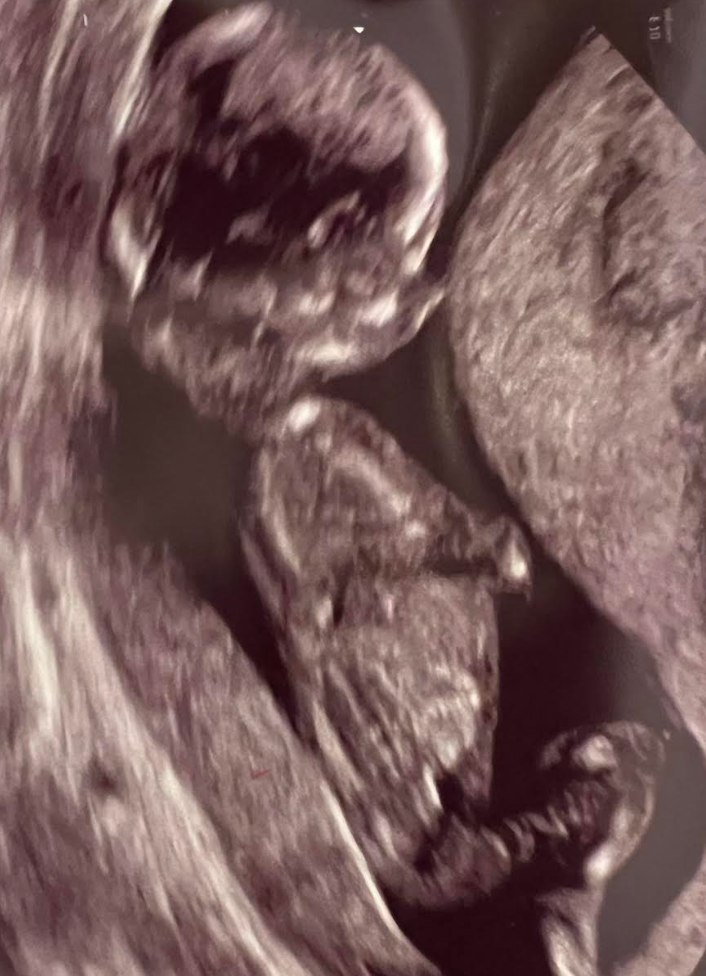

Courtesy of Vaughan Bagley